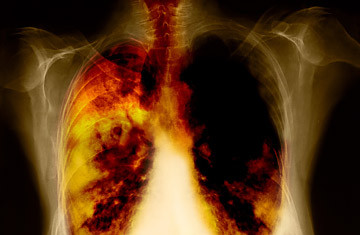

Ung thư phổi: Ung thư phổi được biết đến là căn bệnh ung thư nguy hiểm nhất trên thế giới và cũng là nguyên nhân chết người hàng đầu ở Mỹ.

Tỷ lệ 80-90% mắc căn bệnh này là do tiếp xúc với khói thuốc lá lâu dài, và 10-15% là do do ô nhiễm không khí bao gồm cả hút thuốc thụ động, khí radon, asbestos và các yếu tố di truyền .